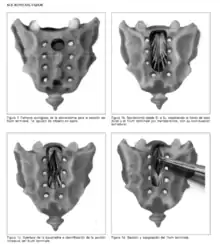

Sección del Filum Terminale

Si la causa de la escoliosis se basa en una lesión neurológica (tensión anómala del filum terminale) y no en las puramente mecánicas (que serían sus efectos) el neurocirujano puede intervenir. El tratamiento que desde 1993 está dando unos resultados esperanzadores es la Sección del Filum Terminale (SFT),[36] ya que atacaría directamente la causa de la enfermedad y no solo sus efectos. Este tipo de intervención varía sus resultados en función del grado de afectación de desviación de la columna, detendría su progresión y puede mejorar el desvío de la columna vertebral especialmente si va acompañada de un adecuada fisioterapia. El tratamiento se realiza bajo anestesia local y sedación. El paciente no precisa corsé de corrección si las curvaturas son menores de 35-40º.